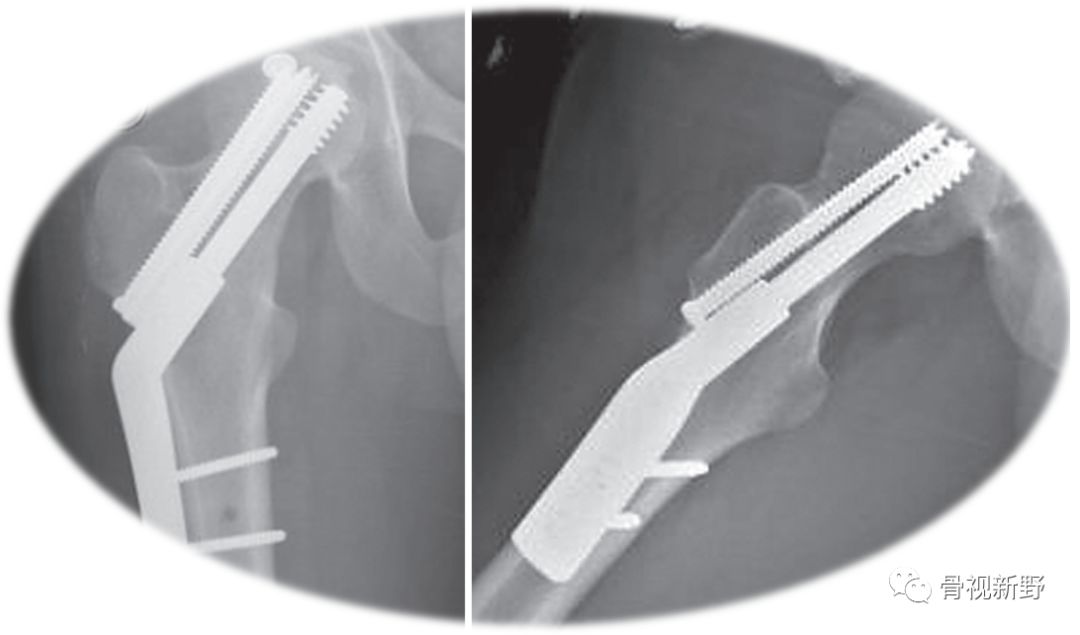

内翻、断钉

传统固定理念——髓内钉固定(Intramedullary nail fixation)

对于合并股骨干骨折的股骨颈骨折,选择髓内钉较其它固定方式有优势。

上图股骨颈骨折空心钉固定失败,内翻畸形、不愈合。行转子间外翻截骨翻修术改用角翼钢板固定(坎贝尔12版,pp2736)。